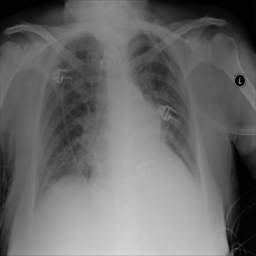

Anomaly detection is the problem of recognizing abnormal inputs based on the seen examples of normal data. Despite recent advances of deep learning in recognizing image anomalies, these methods still prove incapable of handling complex medical images, such as barely visible abnormalities in chest X-rays and metastases in lymph nodes. To address this problem, we introduce a new powerful method of image anomaly detection. It relies on the classical autoencoder approach with a re-designed training pipeline to handle high-resolution, complex images and a robust way of computing an image abnormality score. We revisit the very problem statement of fully unsupervised anomaly detection, where no abnormal examples at all are provided during the model setup. We propose to relax this unrealistic assumption by using a very small number of anomalies of confined variability merely to initiate the search of hyperparameters of the model. We evaluate our solution on natural image datasets with a known benchmark, as well as on two medical datasets containing radiology and digital pathology images. The proposed approach suggests a new strong baseline for image anomaly detection and outperforms state-of-the-art approaches in complex medical image analysis tasks.